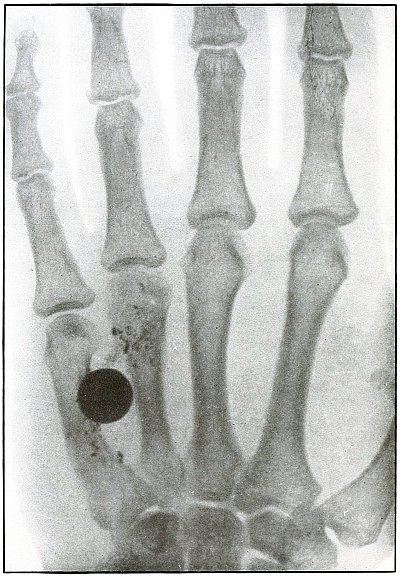

Plate 43.

_

[Pg 97]

Rifle—Plate 43.

UPPER EXTREMITY.

Gunshot Fracture of the Metacarpus.

Wound of entrance, inner aspect of the hand over proximal end of the fifth metacarpal.

Wound of exit, on the outer border of the hand over the distal end of the second metacarpal.

The velocity of the bullet was in mid or long range, as it displaced no fragments, and as it made a point of entrance and exit about the same in appearance.

The wound was infected, which is more frequently the case in the hand than in the forearm.

The treatment is conservative with free incision and drainage in the management of infection. [Pg 98]